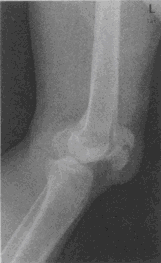

患者,男,24岁。外伤后膝部活动受限,肿胀疼痛。摄左膝部侧位X线片如图所示,影像学诊断为 YZ332_6_37_43.gif

• A.膝关节脱位

• B.胫骨平台骨折

• C.髌骨横断骨折

• D.髌骨粉碎性骨折

• E.胫骨髁间隆突骨折